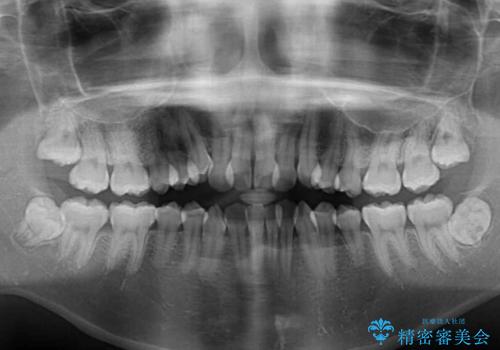

- 八重歯と上下前歯のでこぼこを気にして来院された患者様です。

上下前歯部叢生のスペース獲得のため、上下顎左右小臼歯各1歯(計4本)と全ての親知らずを抜歯して、矯正治療を行うこととしました。

上下の正中位置が大きくずれていたため、治療期間の長期化や正中が合わないまま終了することが予想されましたが、思っていた以上にスムーズに歯が移動し、満足いただける仕上がりとなりました。